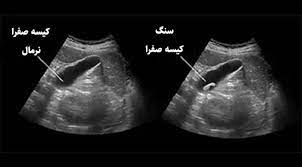

این فوق تخصص گوارش گفت: شایعترین مشکل صفرا، سنگهای کیسه صفراست. این سنگها میتوانند هم داخل کیسه صفرا باشند و هم در مجاری کیسه صفرا قرار داشته باشند بطوریکه ۸۵ درصد موارد سنگ در خود کیسه صفراست و ۱۵ درصد سنگ در مجاری صفراوی تشکیل میشود.

فوق تخصص گوارش در پاسخ به این سوال که شایع ترین علامت سنگ کیسه صفرا چیست؟ افزود: بی علامتی شایعترین علامت سنگ کیسه صفراست و اغلب بصورت تصادفی یافت میشوند. ۷۵ درصد موارد سنگهای درون کیسه صفرا تا آخر عمر بدون علامت باقی می مانند. شایعترین محل درد، زیر دنده سمت راست و روی معده است؛ البته احتمال دارد افرادی با درد شانه و پشت نیز مواجه شوند.

شهریار نیک پور،شایع ترین و بهترین روش تشخیص سنگ کیسه صفرا را سونوگرافی دانست و گفت: سنگ کیسه صفرا پس از علامت دار شدن نیاز به جراحی دارد.